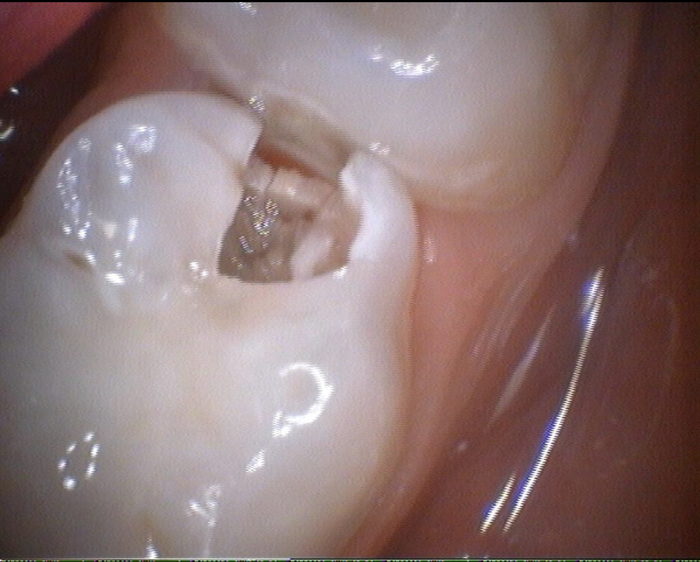

Снимки

Это собственно зуб под удаление молочный

А это тот самый сложный кариес. Как сказала врач БЕЛЫЙ КАРИЕС который очень сложно лечить